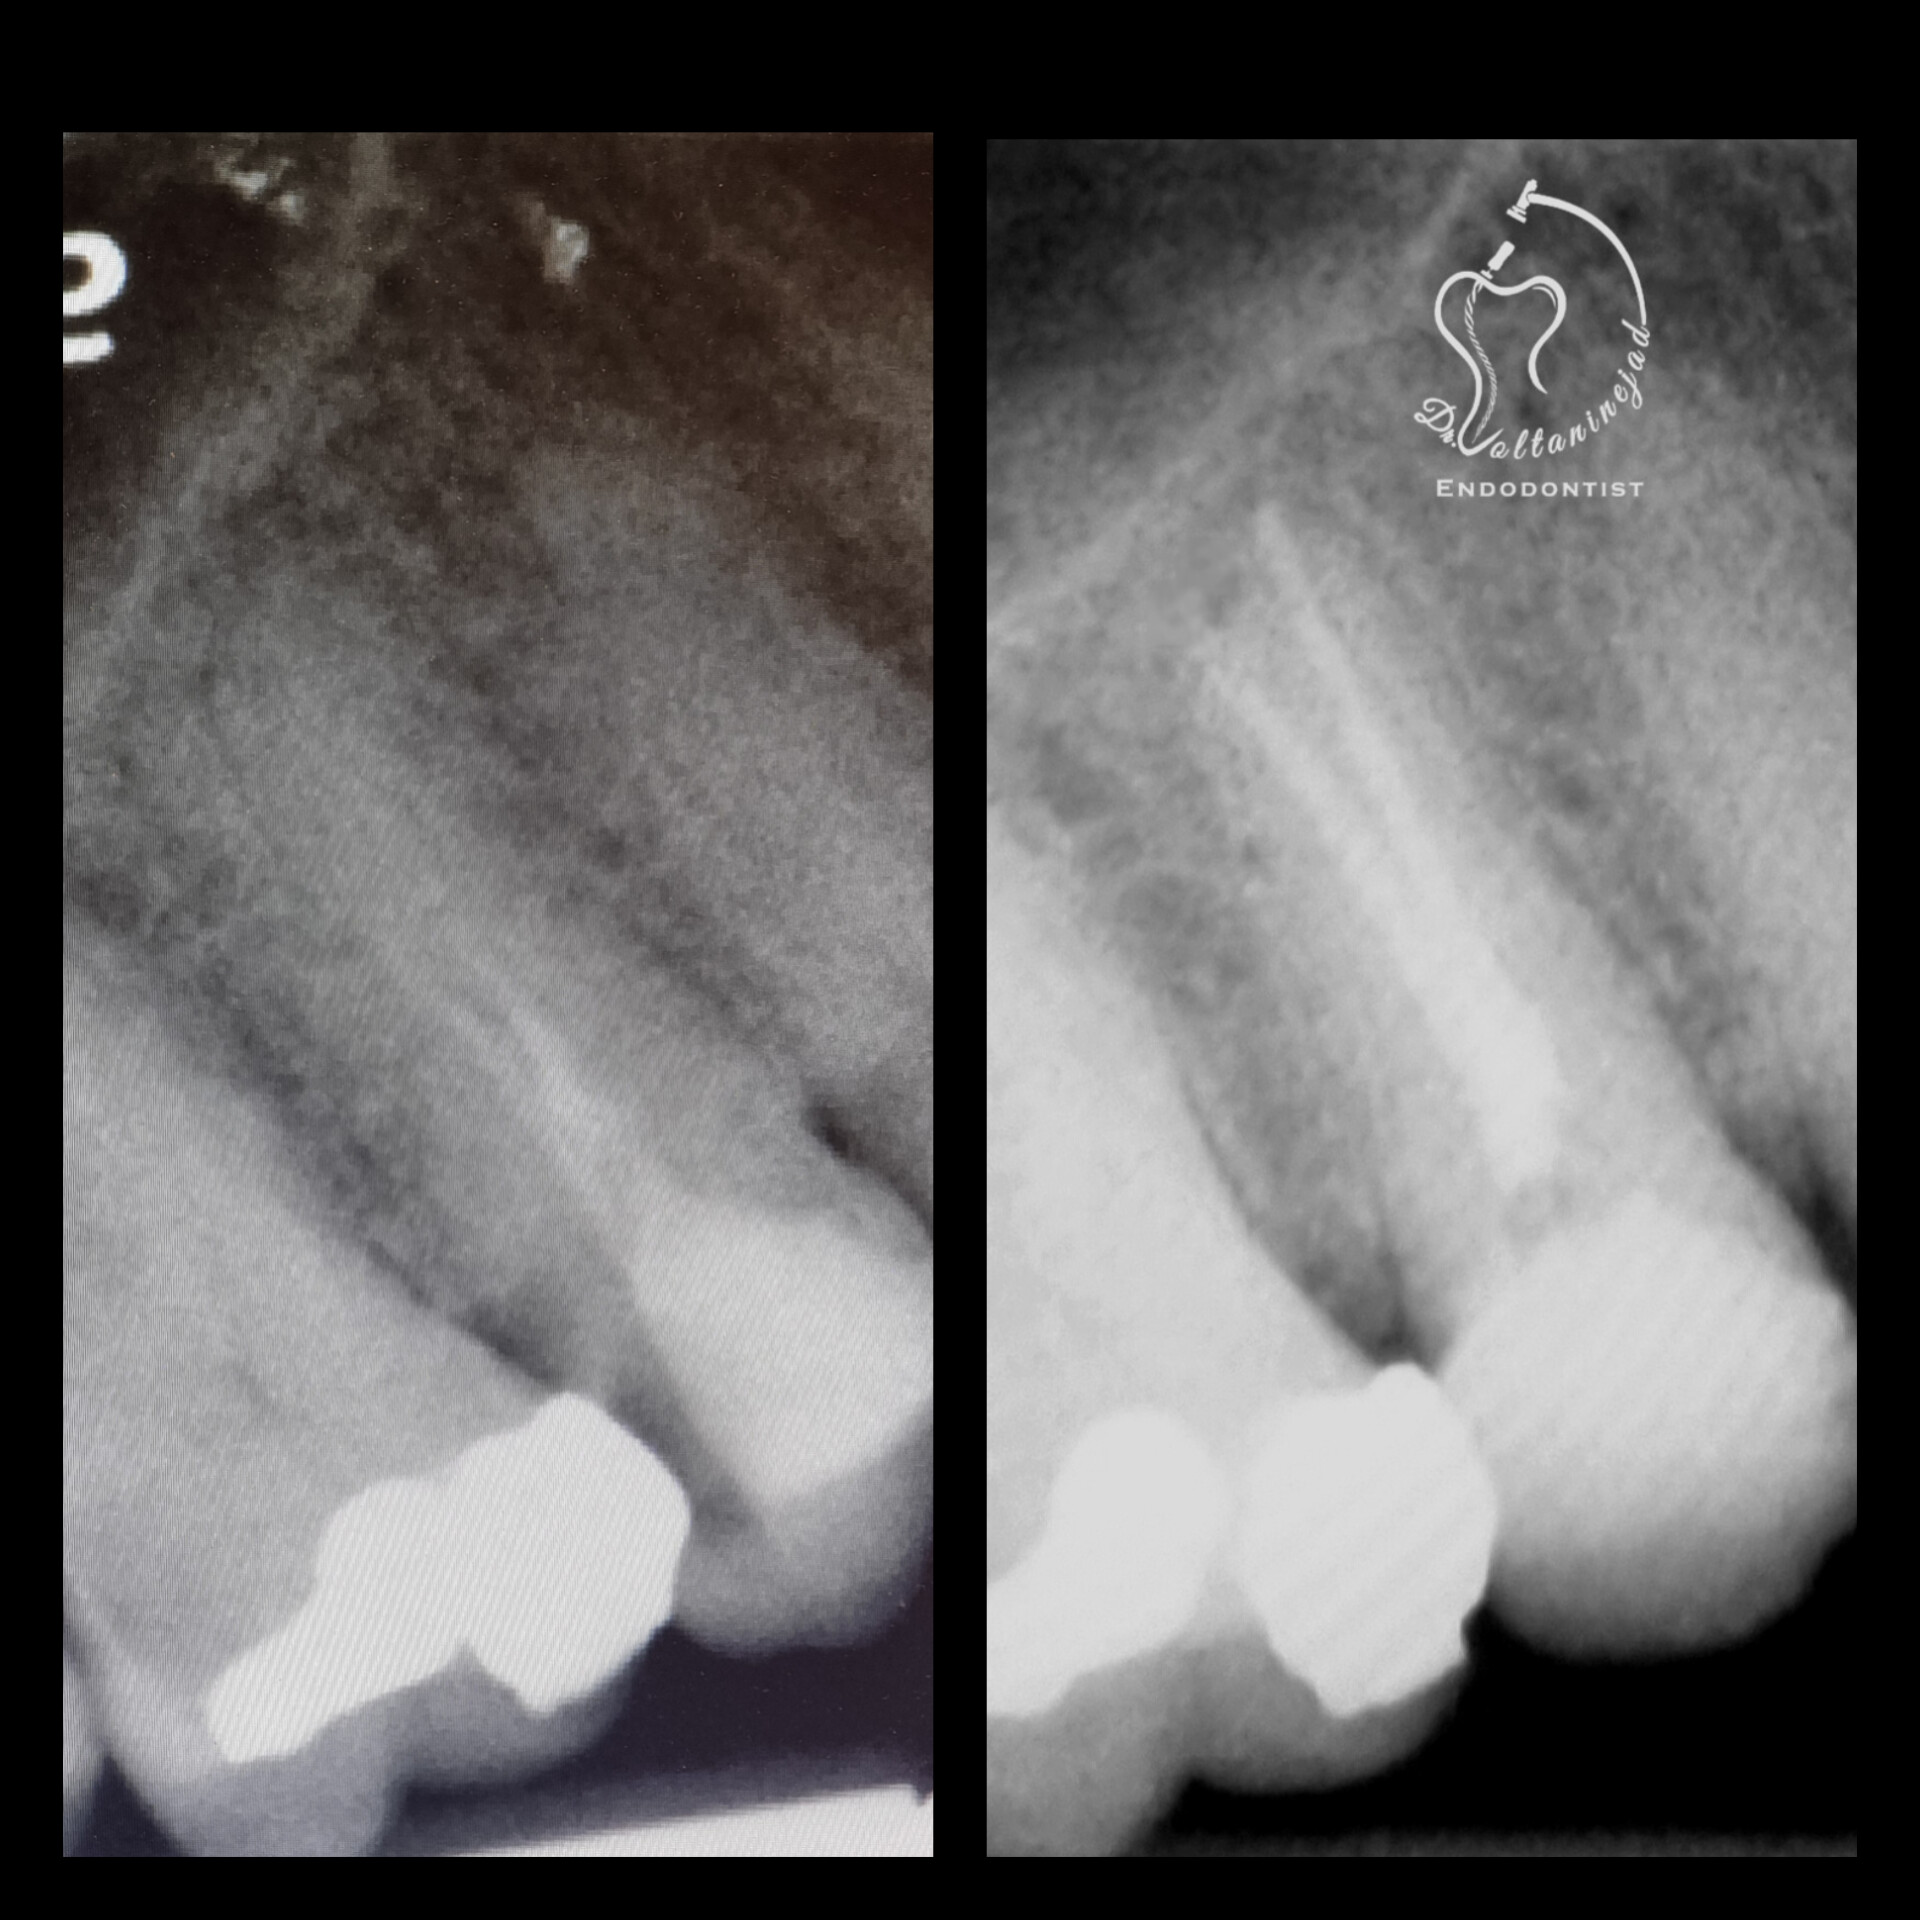

🔹 درمان ریشه مجدد (Retreatment) در دندان پرمولر

• شرح کوتاه: درمان قبلی نامناسب و همراه با عفونت بود. درمان مجدد با میکروسکوپ انجام شد.

• نتیجه: ترمیم ضایعه استخوانی و بازگرداندن دندان به شرایط سالم.

درمان ریشه مجدد پرمولر